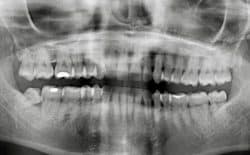

What if the subject was easier third molar impactions with a similarly effective outcome? Continuum 4, November 2nd, 3rd, and 5th: Two evening webinars and all-day Saturday in Dallas. See 3rd & 4th pics (case for GPs and troughing). CLICK HERE